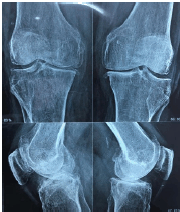

Paciente mulher com 68 anos, IMC 32, apresenta dor crônica em joelhos, com piora progressiva, interferindo na marcha. Ausência de outras queixas articulares. A radiografia simples em incidências anteroposterior e perfil são demonstradas na imagem abaixo.

Diante das características clínicas e radiográficas desta paciente, analise as proposições abaixo e responda o que se pede.

I- A diminuição acentuada do espaço articular sugere o diagnóstico de artrite reumatoide, devendo iniciar o uso de glicocorticoide e metotrexato.

II- A dor certamente não provém da cartilagem, visto ser aneural, estruturas bem inervadas como ênteses, ligamentos e osso subcondral podem ter seus nociceptores estimulados, quer por tração mecânica, quer por mediadores algogênicos como prostaglandina E2, liberada localmente.

III- A obesidade constitui um fator de risco, seja pelo fator mecânico, a impor maior desgaste às estruturas articulares, seja por mediadores inflamatórios, como adipocinas, produzidas no tecido adiposo, que potencializam a inflamação local.

IV- O uso de colágeno hidrolisado tipo II está bem estabelecido como medida terapêutica, no propósito de estimular os condrócitos no restabelecimento do equilíbrio da matriz cartilaginosa e dos proteoglicanos.

V- É necessário ao médico abordar eventuais comorbidades e orientar o seu tratamento, sugerindo atendimento especializado adicional, uma vez que conviver melhor com a senescência e tratar comorbidades contribui para reduzir a perda de força muscular e do equilíbrio.